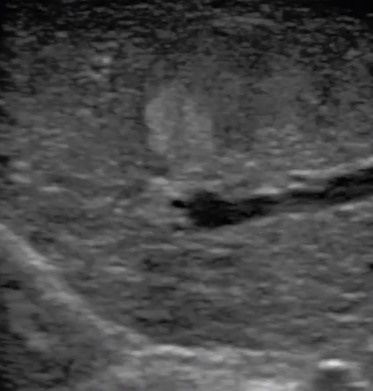

腹腔鏡超聲是超聲技術和腹腔鏡技術的融合,腹腔鏡超聲降低了對超聲探測深度的要求。由微小切口進入手術部位,多角度彎曲可選擇,降低手術難度及風險;與受檢組織器官直接接觸,有效避免氣體干擾。

應用科室:麻醉科、手術室、普外科、泌尿外科、婦產科、腫瘤科、介入科等

腹腔鏡下 肝臟占位